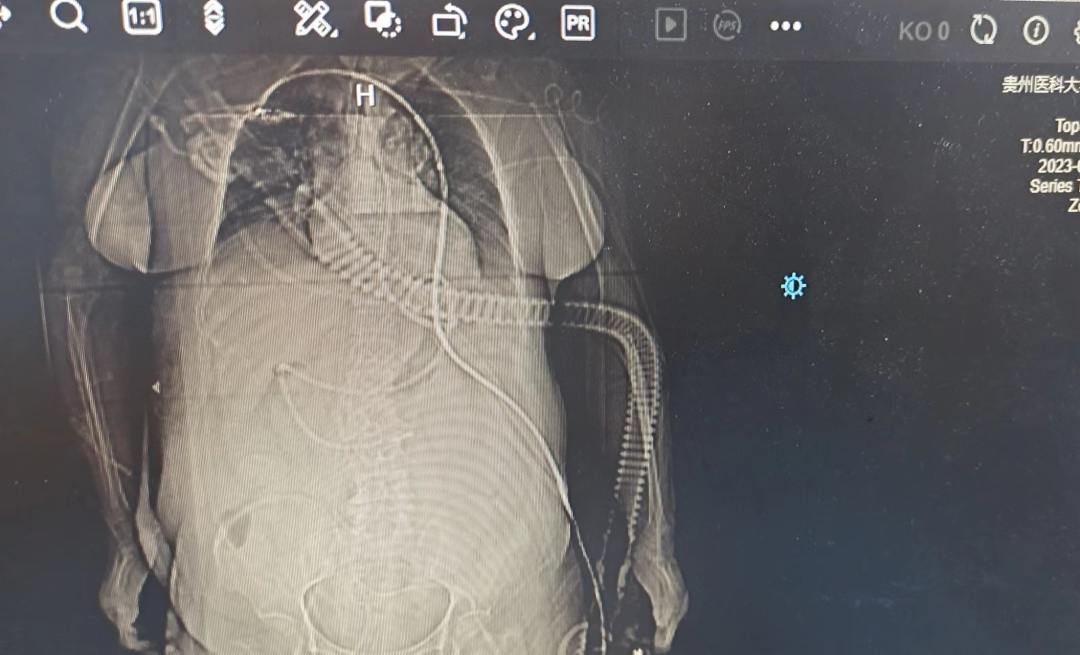

是一种经鼻腔—食管到达胃部,最后插入小肠的鼻饲管道,成人一般插入深度为95-105cm。超声引导下鼻肠管置管术是指在鼻肠管置管过程中,通过对食道、胃窦、幽门、十二指肠区进行超声检查,以实时定位鼻肠管头端,把握鼻肠管的位置及走向。